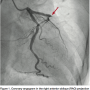

The patient was shifted immediately to the catheterization laboratory after informed consent was obtained for primary percutaneous intervention. Coronary angiography revealed that the left main coronary artery was normal and gave off the large left anterior descending (LAD) and left circumflex (LCX) arteries. The LCX was a non-dominant artery and free of disease. The LAD continued in the anterior interventricular groove with 100% occlusion after the septal branch (Figure 1). The right coronary artery was a nondominant, diminutive vessel arising from the right coronary sinus, ended in the right anterior atrioventricular groove, and was free of disease (Figure 2).